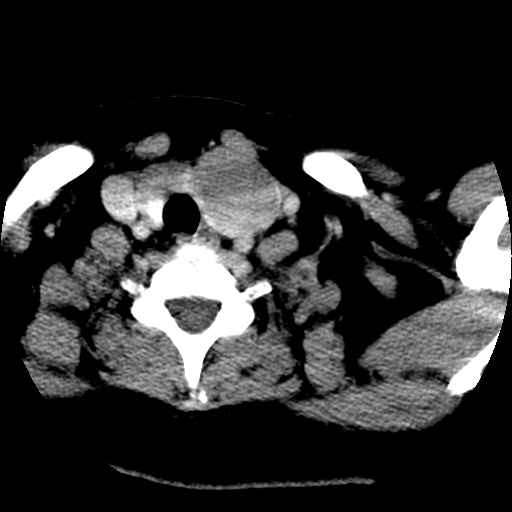

考虑左侧甲状腺结节性甲状腺肿,不排除甲状腺腺瘤。